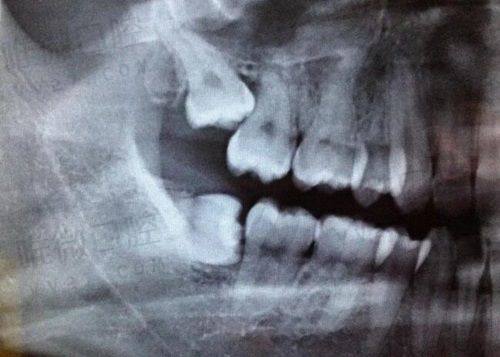

从医院的环境和设备来看,爱齿口腔也做得相当不错。医院的装修风格简洁大方,各个诊疗区域划分得特别清晰,让人一进去就感觉特别舒服。同时,医院引进了精良的口腔诊疗设备,像数字化口腔全景机、种植机等。这些设备不仅能让医生更正确地诊断病情,还能提高治疗的成效和安心性。